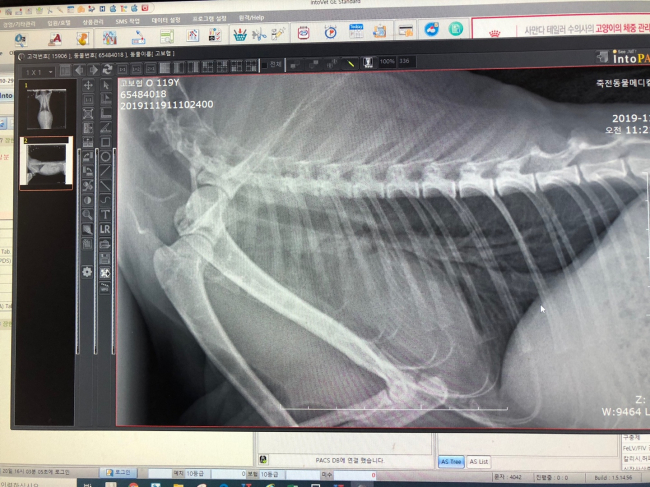

치료중 대상묘